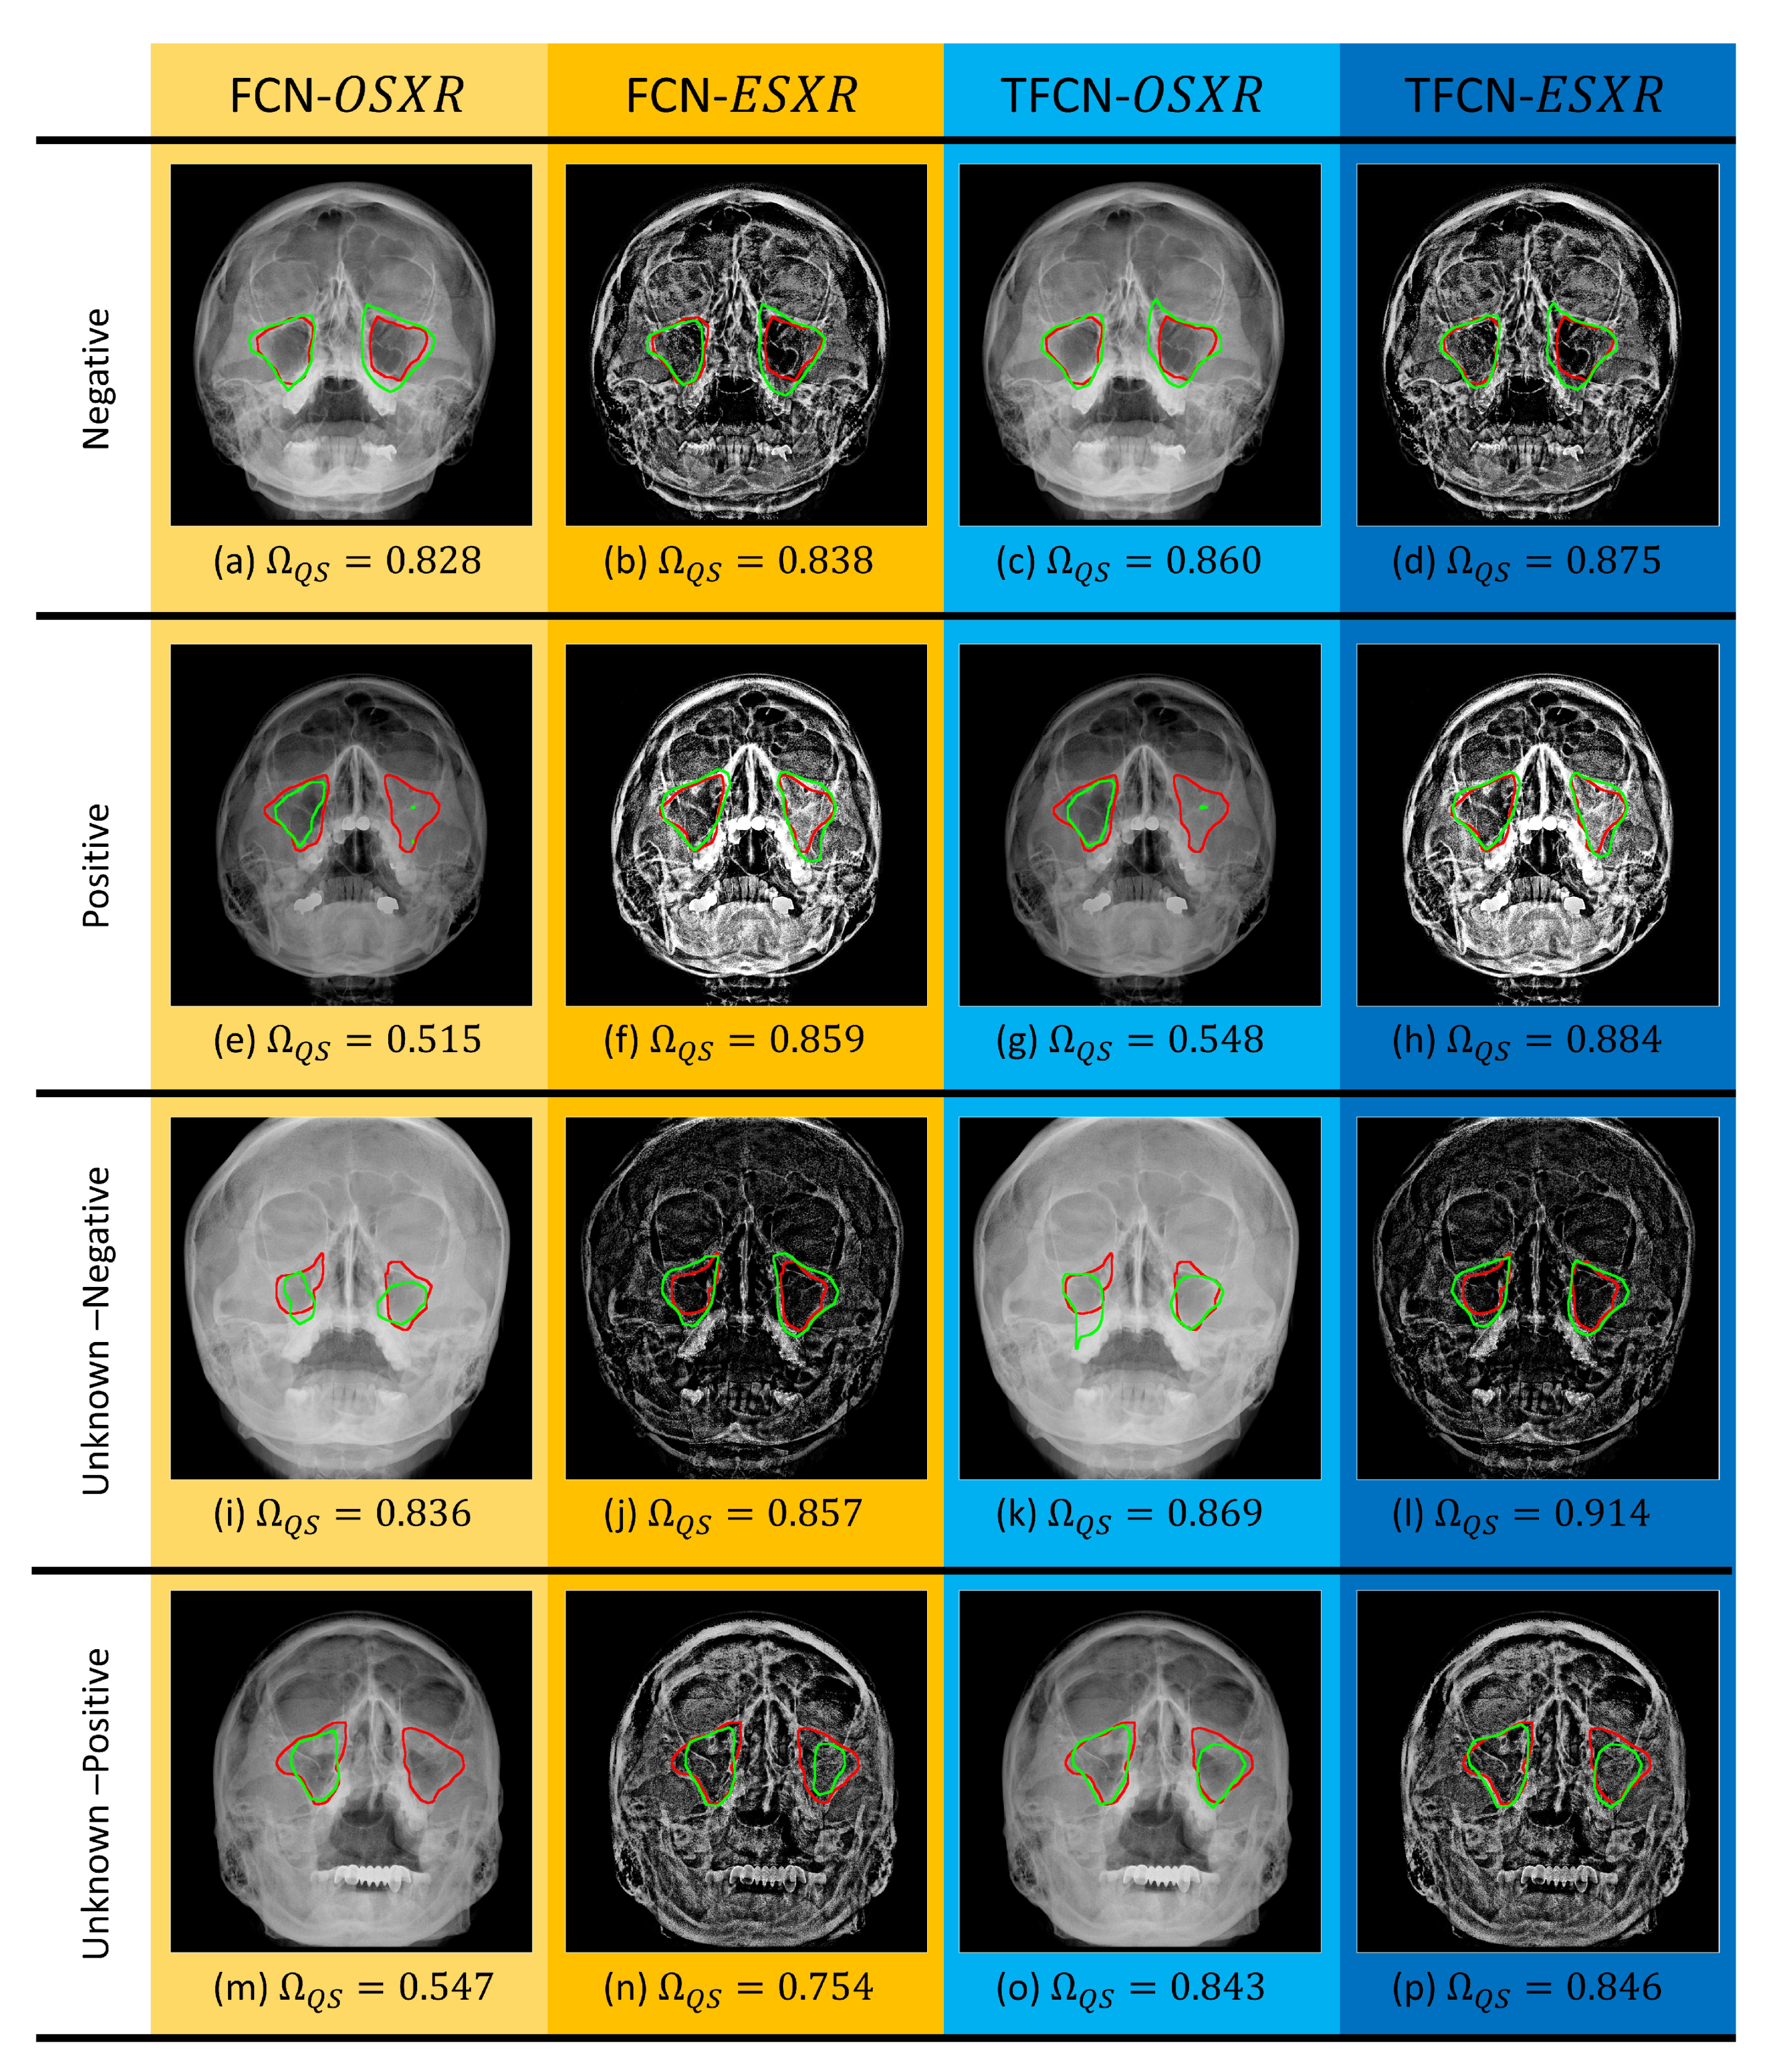

In both FCN [16] and T-FCN, with either or dataset, steep scores for negative SXRs were achieved. As shown in Figure 4a–d, all combinations successfully segmented both left and right maxillary sinuses due to the features within the cavity walls can be easily identified as there is no discrepancy that attenuates those features.

Figure 4.

A montage of segmentation results using the FCN [16] against the T-FCN with all combinations of training and test datasets as shown above from (a–p).

Contrary to the prior example of negative cases, the positive cases of maxillary sinusitis induce complex textures within the inflamed sinus(es). In Figure 4e–h, the subject suffered acute sinus infection that causes substantial mucous accumulation within the left maxillary sinus, while the right maxillary sinus remained normal. This specific condition has made the cavity walls within the left maxillary sinus are vaguely depicted. Trained on dataset, both methods adversely failed to segment the left maxillary sinus on the original SXR image shown in Figure 4e,g, respectively; yet, the right maxillary sinus was correctly segmented with better contour resemblance by T-FCN.

On the other hand, both FCN and T-FCN that were trained on dataset generated better segmentation results, where both left and right maxillary sinuses were correctly segmented as shown in Figure 4f,h, respectively. Therefore, based on the comparison between methods trained with and methods trained with , the observation suggested that the ToMA algorithm applied on SXRs from the dataset to generate the dataset is indeed effective in enhancing the performance of segmentation methods as the features are visually bolstered. Compared to FCN, the proposed T-FCN still showed its merit as FCN yields higher amount of false positive pixels on the left maxillary sinus because of strong boundary features from the lower zygomatic bone, which made false contours. Essentially, the FCN [16] is less robust against false contour(s) that may directly affect the actual contour of the maxillary sinuses compared to the proposed T-FCN.

For cases with dubious diagnosis in the unknown folds (including unknown-negative and unknown-positive cases), the proposed T-FCN with dataset is consistent to be the most optimum combination to segment maxillary sinuses from the SXR images. In particular, the example in Figure 4i–l, shows that the proposed T-FCN trained with either or outperformed the prior FCN [16] trained with the corresponding dataset. The prior FCN with dataset generated a significant amount of false predictions (shown in Figure 4i) because of low contrast condition after the image acquisition. On the other hand, the proposed T-FCN with dataset generated segmentation result with most resemblance to the contour reference on both left and right sinuses (Figure 4l). The proposed ToMA that enhances the contrast ratio of the SXR images helped the T-FCN to extract and process the regions’ features correctly for accurate prediction outcomes.

Contrary to the prior example, instances in Figure 4m–p illustrate the unknown-positive with (a) dubious regions’ contours (because of infection) and (b) particularly unusual pose of the subject patient that obstructed the visibility of the left maxillary sinus. Subjectively, the prior FCN with dataset failed to segment the left maxillary sinus (Figure 4m), while the other combinations of methods and datasets generated segmentation with better predictions (Figure 4n–p). For either right or left maxillary sinus, the proposed T-FCN with provides the best segmentation among the others.